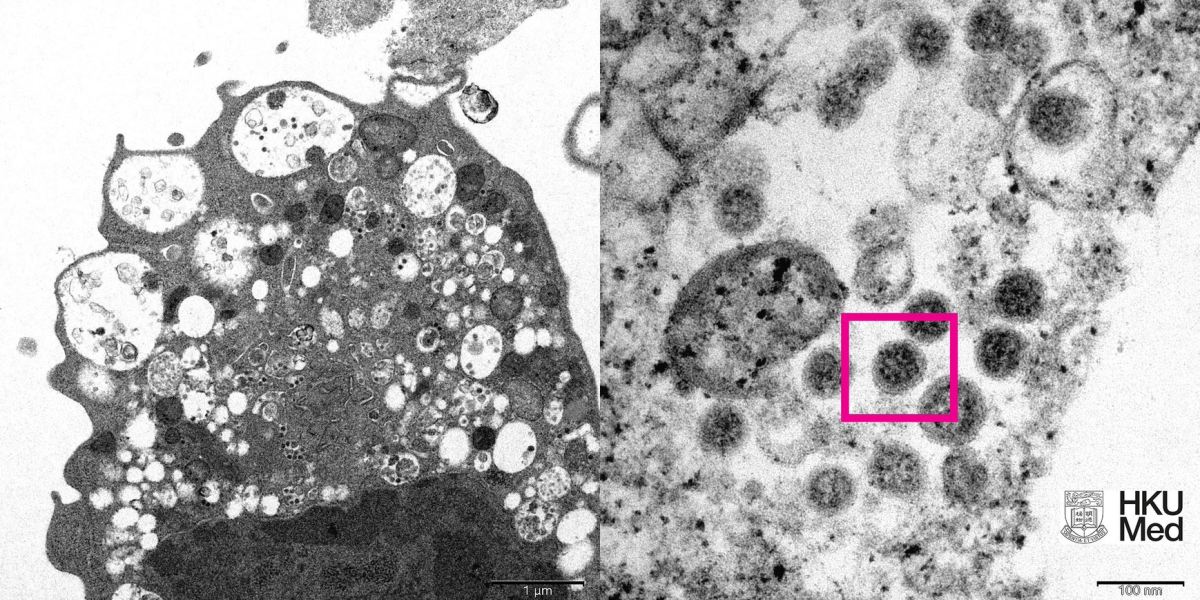

(圖左)低倍電子顯微鏡下感染新型冠狀病毒Omicron變異株後的猴腎細胞(Vero E6)。照片顯示細胞受損,腫脹囊泡,囊泡內含有黑色小病毒顆粒;(圖右)高倍電子顯微鏡下受感染的Vero E6細胞。照片顯示病毒顆粒,其表面呈現皇冠形的刺突蛋白(見紅框)。(香港大學醫學院供圖)

研究人員在低倍電子顯微鏡下,觀察感染新型冠狀病毒Omicron變異株後的猴腎細胞(Vero E6)。照片顯示細胞受損,腫脹囊泡,囊泡內含有黑色小病毒顆粒;在高倍電子顯微鏡下,觀察受感染的Vero E6細胞,照片顯示病毒顆粒表面呈現皇冠形的刺突蛋白。